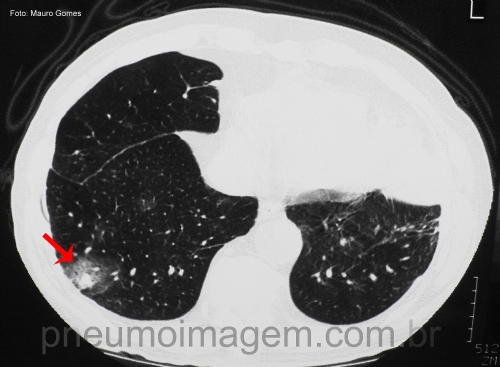

CASO CLÍNICO #43

Esse sinal tomográfico está associado a uma grave complicação em imunocomprometidos. Qual o nome do sinal e a qual doença ele se relaciona? Deixe os seus comentários abaixo!

This tomographic signal is associated with a serious complication in immunocompromised patients. What is the name of the sign and what disease does it relate to? Write your comments below!